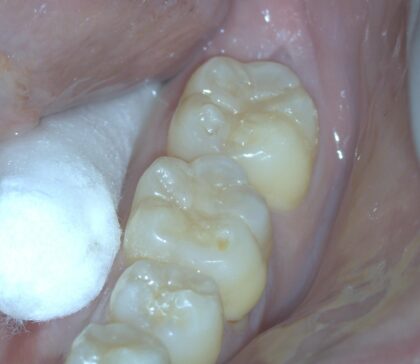

見えづらいですが、矢印の先の歯の溝に深いむし歯が存在します。

むし歯を取ります。プラスチックを流し込むときに固まらないように光源を黄色くしています。

プラスチックを固めた後、かみ合わせに問題ないかチェックします。

歯にテクスチャをつけて完成です。

きれいに詰めることができれば天然の歯と遜色ない見た目にすることができます。